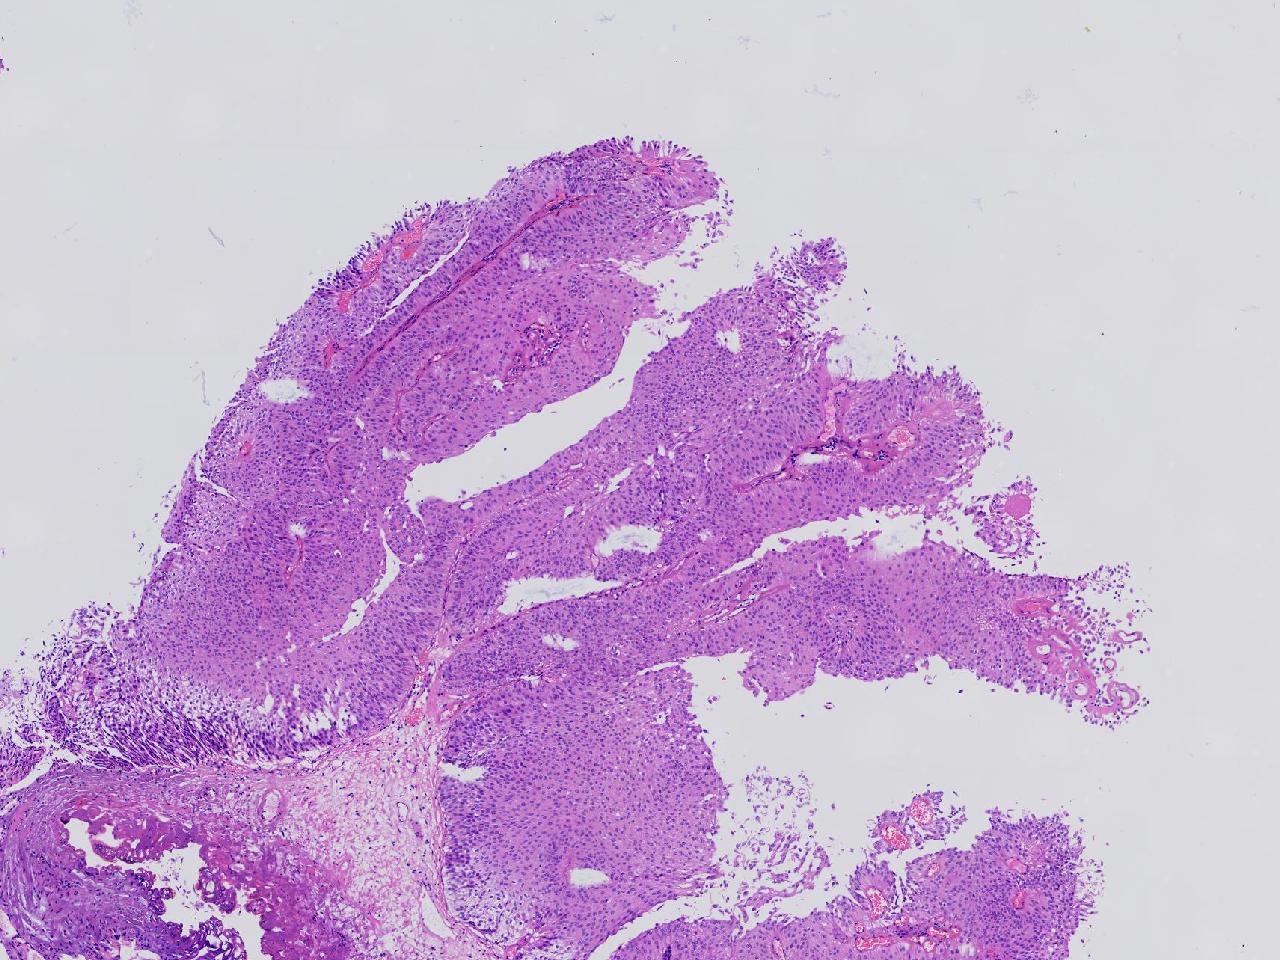

男,79岁,膀胱肿物。

膀胱肿物

灰白色不整形软组织多块,2X1X1厘米。

考虑:乳头状尿路上皮癌

考虑低级别,非浸润。

乳头状尿路上皮癌,低级别。

这几张图片上没有看到明确的浸润。